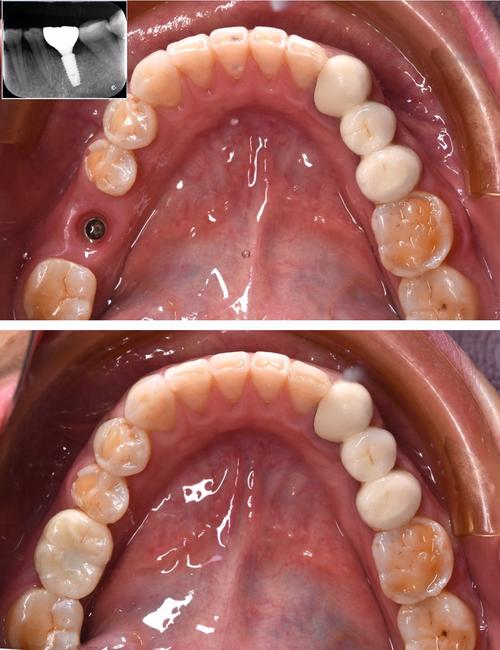

- 术前评估复杂: 种植牙前需要进行详细的检查,包括口腔检查、全景片(曲面断层片)、CT(锥形束CT),CT是必不可少的,它能精确测量牙槽骨的高度、宽度、密度,以及神经管、上颌窦等重要解剖结构的位置,这是制定安全、精准手术方案的基础。

- 植入: 将种植体旋入或压入窝洞中。

- 微创化趋势: 现在的种植技术越来越微创,如即刻种植、微创种植、数字化导板种植等,可以减少创伤、缩短手术时间、加速恢复。